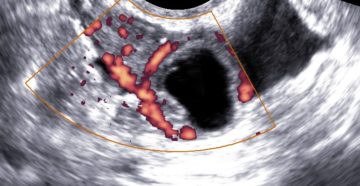

В яичнике жидкостное образование что это Яичники у женщин — это парные органы, которые отвечают…